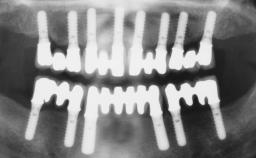

An 83-year-old male patient requested treatment for his existing maxillary complete overdenture and mandibular complete denture. He reported no general medical conditions of significance that would affect his dental treatment and was taking no prescription medication. He denied suffering from oral pain and displayed no evidence of parafunctional habits or temporomandibular joint disorder. Oral and radiographic evaluation revealed two retained maxillary teeth (13 and 15) supporting prefabricated ballshaped attachments. Both teeth were mobile and associated with active periodontal disease and extensive dental caries; these were considered non-restorable and were recommended for extraction. The patient’s existing complete maxillary and mandibular prostheses were approximately 2 years old. He was very satisfied with the appearance of both prostheses. His chief complaint was related to the instability and lack of retention associated with the existing mandibular prosthesis.

# of Implants | 2 |

Type of Implants | Reduced-Diameter|Two-Piece |